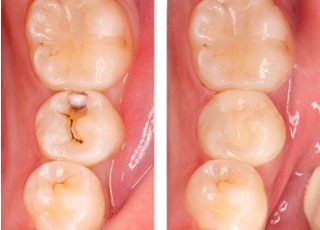

つめ物・かぶせ物

ニーズに合わせた材料と治療法

歯の詰め物やかぶせ物には、現在も保険適用の金属が多く使われています。しかし、健康意識の高まりや審美的な感覚の変化から、目立つ銀歯や金属色に抵抗を感じる方が増えてきました。

当院では、患者さま一人ひとりのご希望やライフスタイルに合わせて、自然な見た目に近づけるための治療法や材料をご提案しています。

セラミックなどの審美性に優れた素材をはじめ、機能性・耐久性を考慮した選択肢もご用意しています。

お口の状態や治療内容によっては、その日のうちに処置が可能なケースもあります。